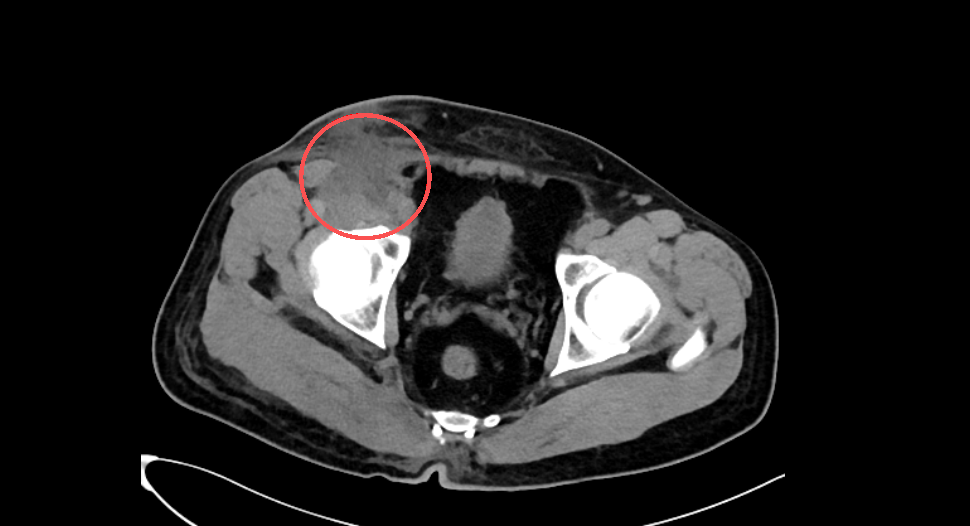

术前ct照